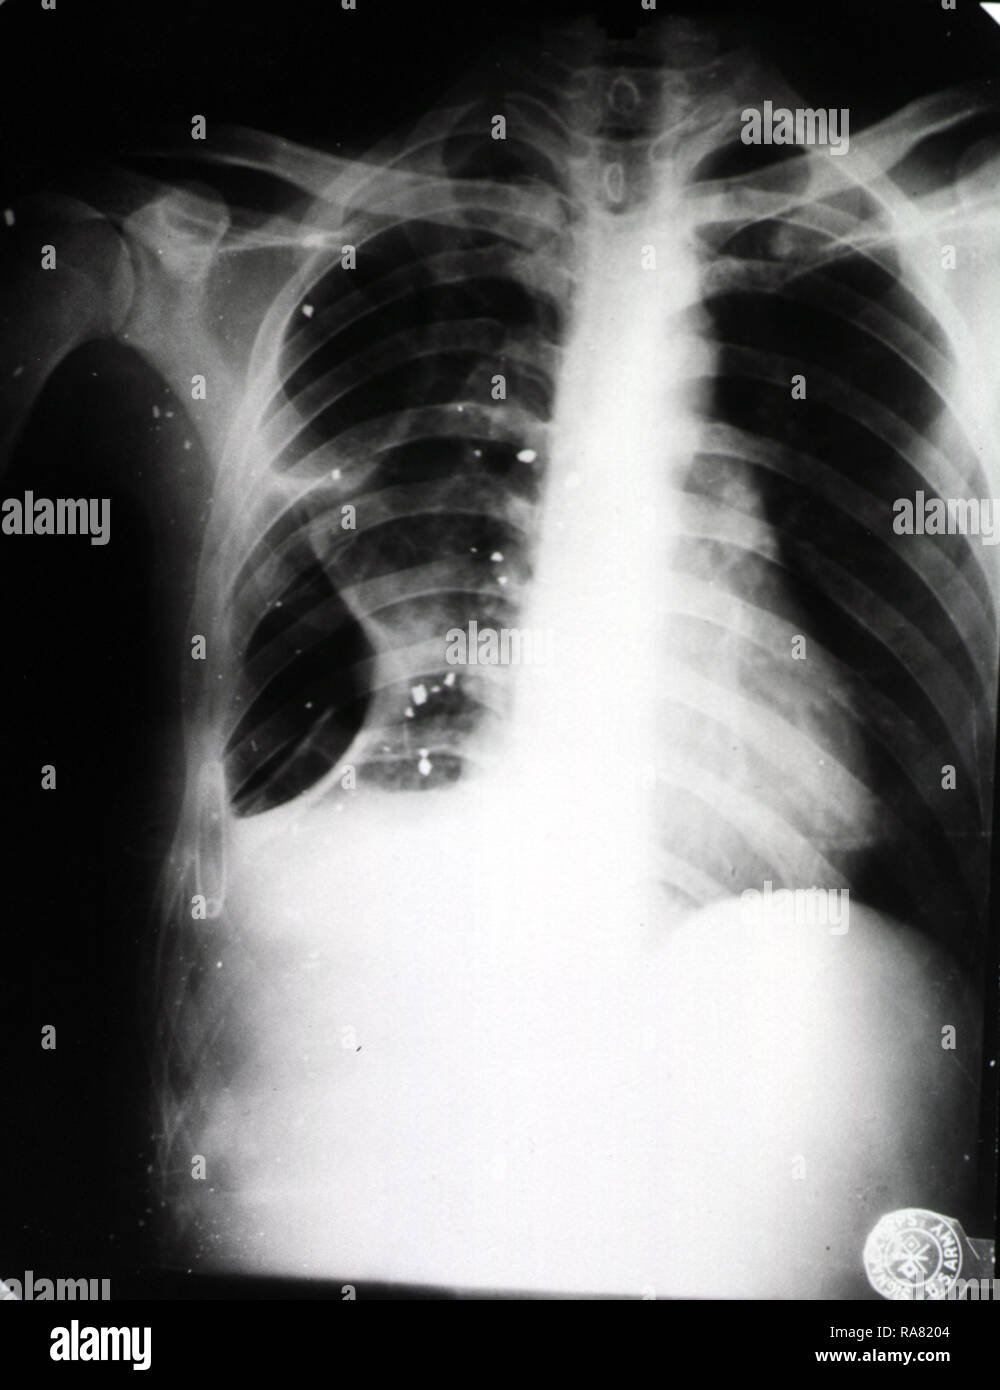

From www.alamy.com

Chest Wound High Resolution Stock Photography and Images Alamy Crushing Chest Wound A chest injury can cause a condition called pneumothorax, which happens when air becomes trapped in the chest, causing the lung to. The diaphragm can rise up to the level. Penetrating trauma — such as from a gunshot or a knife wound, where an object punctures the chest wall. Do not apply heat over open. Blunt chest trauma — such. Crushing Chest Wound.

From www.researchgate.net

Chest Xray taken in the trauma bay showing bullet shrapnel overlying Crushing Chest Wound Blunt chest trauma — such as from sport, a punch or kick, a fall or car accident. An open pneumothorax allows air to enter during inspiration and exit during expiration causing the lung to collapse and fall away from the chest wall creating a pleural. Crush injury — crush injury is the result of physical trauma from prolonged compression of. Crushing Chest Wound.